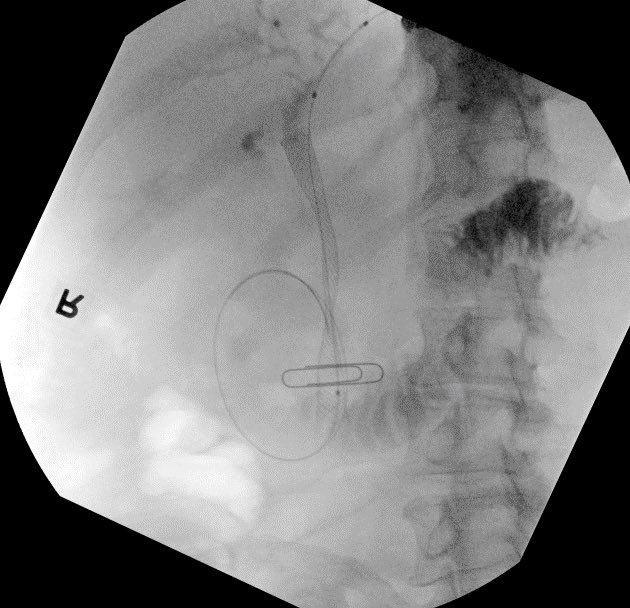

Failed ERCP due to inability to reach major papilla from tumor infiltration into duodenum. Tumor prohibited CDS placement in bulb. Pt declined PTBD and elected for attempt at antegrade biliary stent placement via EUS over HGS. After needle puncture and wire placement we entered